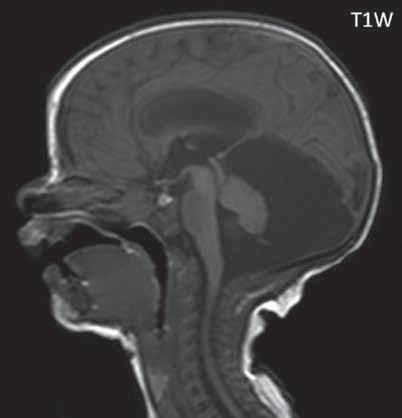

I.1.8 Dandy-Walkerova malformace (D-W variant, D-W komplex, D-W spektrum )

V současné odborné literatuře je nejčastěji užíván termín D-W spektrum, který snad nejlépe vyjadřuje velmi široké možnosti vrozených změn zadní jámy lební. Mezi tuto skupinu cystických malformací zadní jámy lební pak řadíme klasickou malformaci D-W a její varianty, mega cisterna magna, arachnoidální cystu zadní jámy lební a retrocerebelární vak (Blake’s pouch cysta). Zařazení malformace do určité klinické jednotky není někdy jednoznačné, proto je možná výhodnější a přesnější vycházet z přesného popisu zobrazených změn. Příčina D-W malformace není známa, nabízejí se dvě hypotézy: 1. nepropustná spodina IV. komory, eventuálně uzávěr nebo pozdní otevření otvorů, kterými proudí likvor ze IV. komory. 2. primární hypogeneze mozečku. Embryonální vývoj mozečku ze všech hlavních struktur mozku trvá nejdelší dobu, a proto je velmi vulnerabilní k různým patologickým příčinám po dlouhou dobu svého vývoje.

Zobrazení

D-W malformace je charakterizována hypoplazií vermis mozečku, rozšířením IV. mozkové komory, která se často cysticky vyklenuje dorzálně a může imitovat arachnoidální cystu, rozšířením zadní jámy lební a vysokým úponem tentoria s confluens sinum nad lambdovým švem. Okcipitální kost může být vlivem tlakových změn remodelována, existují i případy s porušením její kontinuity a encefalokélou. Hydrocefalus pozorujeme v 80 %, častá je přítomnost dysgeneze corpus callosum, schizencefalie.

D-W variant byl vyčleněn pro případy, kdy všechny základní příznaky nemusí být plně vyjádřeny nebo může některý zcela chybět. Bývá přítomna hypoplazie mozečku, což je dominantní příznak, IV. komora je obvykle rozšířena, někdy pozorujeme, že tvarem připomíná na axiální řezu „klíčovou dírku“, zadní jáma lební naopak rozšířena nebývá.

Mega cisterna magna je struktura likvorového signálu, lokalizována dorzálně a kaudálně od mozečku, není doprovázena hypoplazií mozečku, rozšířením IV. komory ani hydrocefalem, někdy může být tlakem zeslabená lamina interna lebky v zadní jámě lební. Diferenciální diagnostika mezi mega cisterna magna a arachnoidální cystou je mnohdy obtížná a může nám pomoci CT cisternografie (chybí nebo pozdní pronikání kontrastní látky do arachnoidální cisterny), určité informace může přinést MR vyšetření pulzace likvoru.

Retrocerebelární vak (Blake’s pouch cysta) vzniká embryonálně vyklenutím části stropu IV. komory (velum

mediale superius) do cisterny magna (vak je vyplněn likvorem, chybí foramen Magendii). Je charakterizován rozšířenou a široce otevřenou IV. komorou, která komprimuje bazální cisterny, hypoplazie vermis mozečku naopak není přítomna. Široce komunikující IV. komora (někdy obsahuje choroidální plexus), přičemž komunikace mezi komorovým systémem a subarachnoidálními prostory je pouze přes laterální foramina Luschkae.

Obr. I.1.8a Dandy-Walkerova malformace, rozšířená IV komora (tvar klíčové dírky)

Obr. I.1.8b Dandy-Walkerova malformace, rozšířená IV komora široce komunikující s cisterna magna, hypotrofie mozečku (snímky zapůjčeny z archivu prim doc MUDr M Mechla, Ph D, MBA)

Obr. I.1.8c Dandy-Walkerova malformace, rozšířená IV komora široce komunikující s cisterna magna, hypotrofie mozečku (snímky zapůjčeny z archivu prim doc MUDr M Mechla, Ph D, MBA); stejný pacient jako na obr I 1 8b

Obr. I.1.8d Dandy-Walkerova malformace, rozšířená IV komora široce komunikující s cisterna magna, hypotrofie mozečku, vysoký úpon tentoria (šipka) (snímky zapůjčeny z archivu prim doc MUDr M Mechla, Ph D, MBA); stejný pacient jako na obr I 1 8b, c

Obr. I.1.8e Dandy-Walkerovo spektrum (hypoplazie vermis, IV komora je rozšířená a široce zeje) (snímky zapůjčeny z archivu as MUDr J Lisého, CSc )

Obr. I.1.8f Dandy-Walkerovo spektrum (hypoplazie vermis, IV komora je rozšířená a široce zeje) (snímky zapůjčeny z archivu as MUDr J Lisého, CSc ); stejný pacient jako na obr I 1 8e

Obr. I.1.8g Dandy-Walkerovo spektrum (hypoplazie vermis, IV komora je rozšířená a široce zeje), (snímky zapůjčeny z archivu as MUDr J Lisého, CSc ); stejný pacient jako na obr I 1 8e, f

Obr. I.1.8h Mega cisterna magna

Obr. I.1.8ch Retrocerebelární vak (Blake’s pouch cyst), široce komunikující IV komora, chybí foramen Magendii